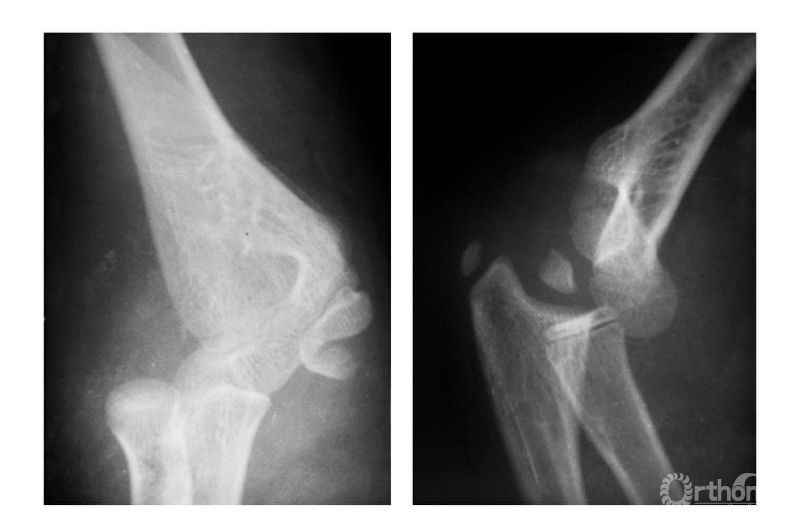

Ⅳ度损伤:

例1:肘关节外后脱位并肱骨内上髁撕脱骨折,骨块移向尺肱关节间(图9)。

图9